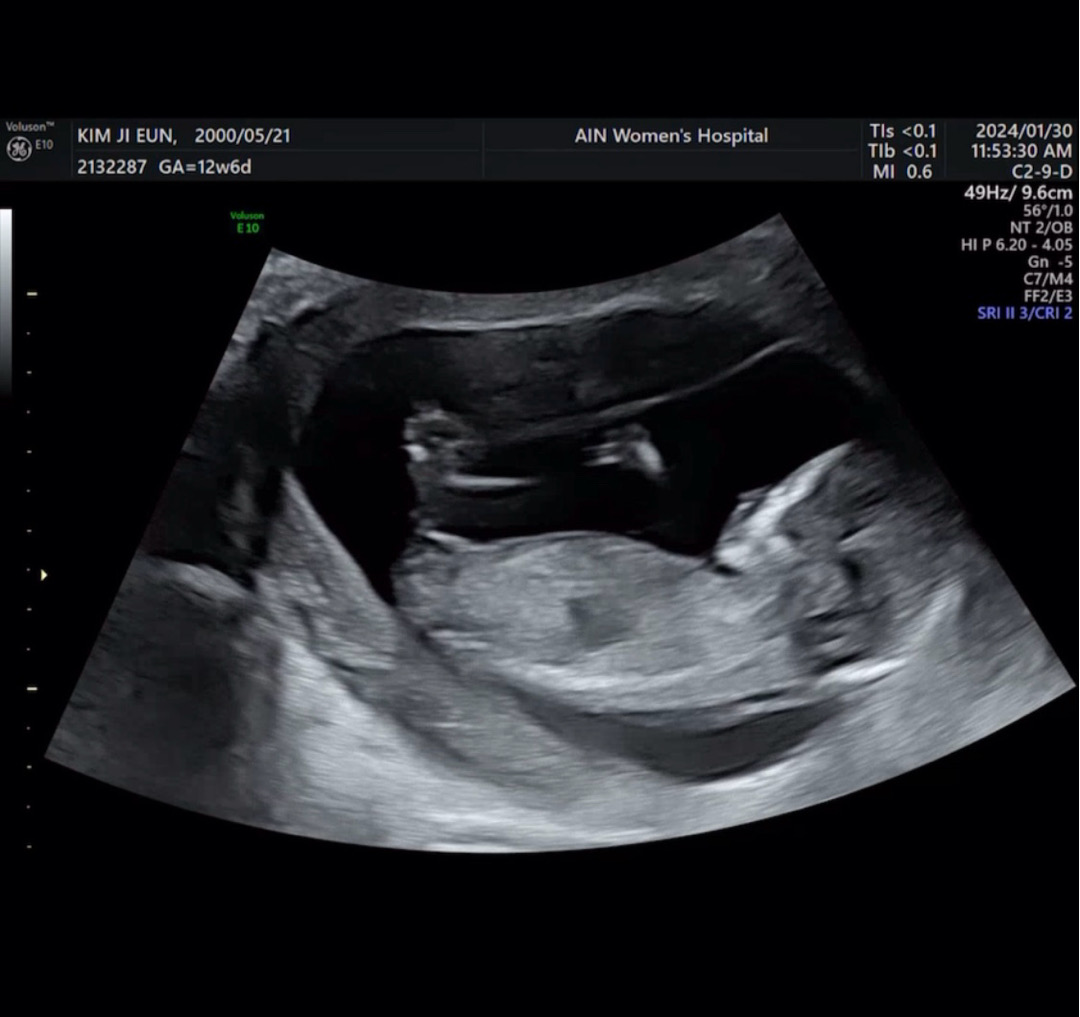

조금 늦은 12주6일차 초음파!

제가 보기엔 딸같은데 어떤가요?? 9주초음파봤을때도 그냥 느낌에 딸인가? 싶었는데 12주6일에 다리사이가 생각보다 깨끗하더라구요 지금 구별이 어려울수도 있지만? ㅋㅋㅋ 남편이 딸을 너무너무 기다려서 아들이면 서운해할까봐 아들이라고 세뇌(?) 시키고있는데 다른 분들은 어떻게 하세요?

지금은 딸이던아들이던 둘다 생식기가 돌출되어 있습니다. 돌출여부로는 판단이 안될거에요 다만 다른분들께서 보는 각도법 ? 등으로 유추해볼순있을듯요..(과학적 근거가 있는진 모르겠어요)